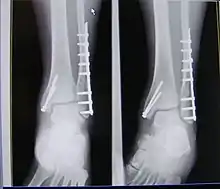

| X-ray of trimalleolar fracture repair before and after ORIF surgery | |

A trimalleolar fracture also known as Cotton fracture,[1] is a fracture of the ankle that involves the lateral malleolus, the medial malleolus, and the distal posterior aspect of the tibia, which can be termed the posterior malleolus. The trauma is sometimes accompanied by ligament damage and dislocation.[2]

Treatment

Surgical repair using open reduction and internal fixation is generally required, and because there is no lateral restraint of the foot, the ankle cannot bear any weight while the bone knits. This typically takes six weeks in an otherwise healthy person, but can take as much as twelve weeks. Non-surgical treatment may sometimes be considered in cases where the patient has significant health problems or where the risk of surgery may be too great.[2]